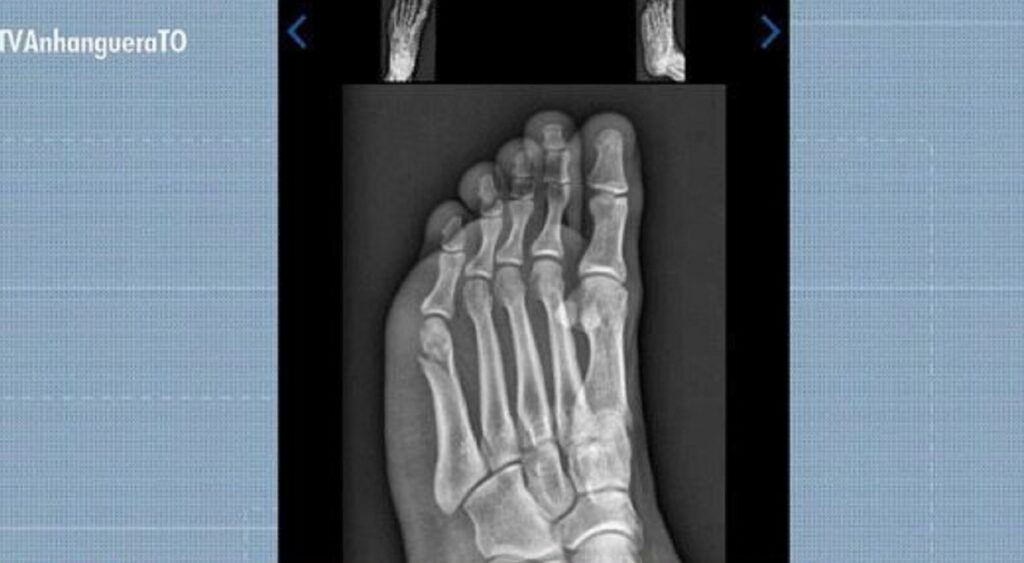

Candidato faz teste físico da PM com fratura no pé e consegue aprovação: ‘Pensei que não ia conseguir’

Candidato quebra pé dias antes do TAF da Polícia Militar

Um jovem concurseiro de Gurupi, no sul do Tocantins, conseguiu ser aprovado no Teste de Aptidão Física (TAF) da Polícia Militar mesmo com o pé quebrado. A prova aconteceu 30 dias após Gabriel Santos Rodrigues, de 22 anos, cair do telhado da própria casa enquanto trocava a boia da caixa d’água.

Gabriel Santos Rodrigues foi aprovado no TAF da PMTO mesmo com fratura no pé

Reprodução/TV Anhanguera

Concurseiro concluiu prova de corrida do TAF com fratura no pé